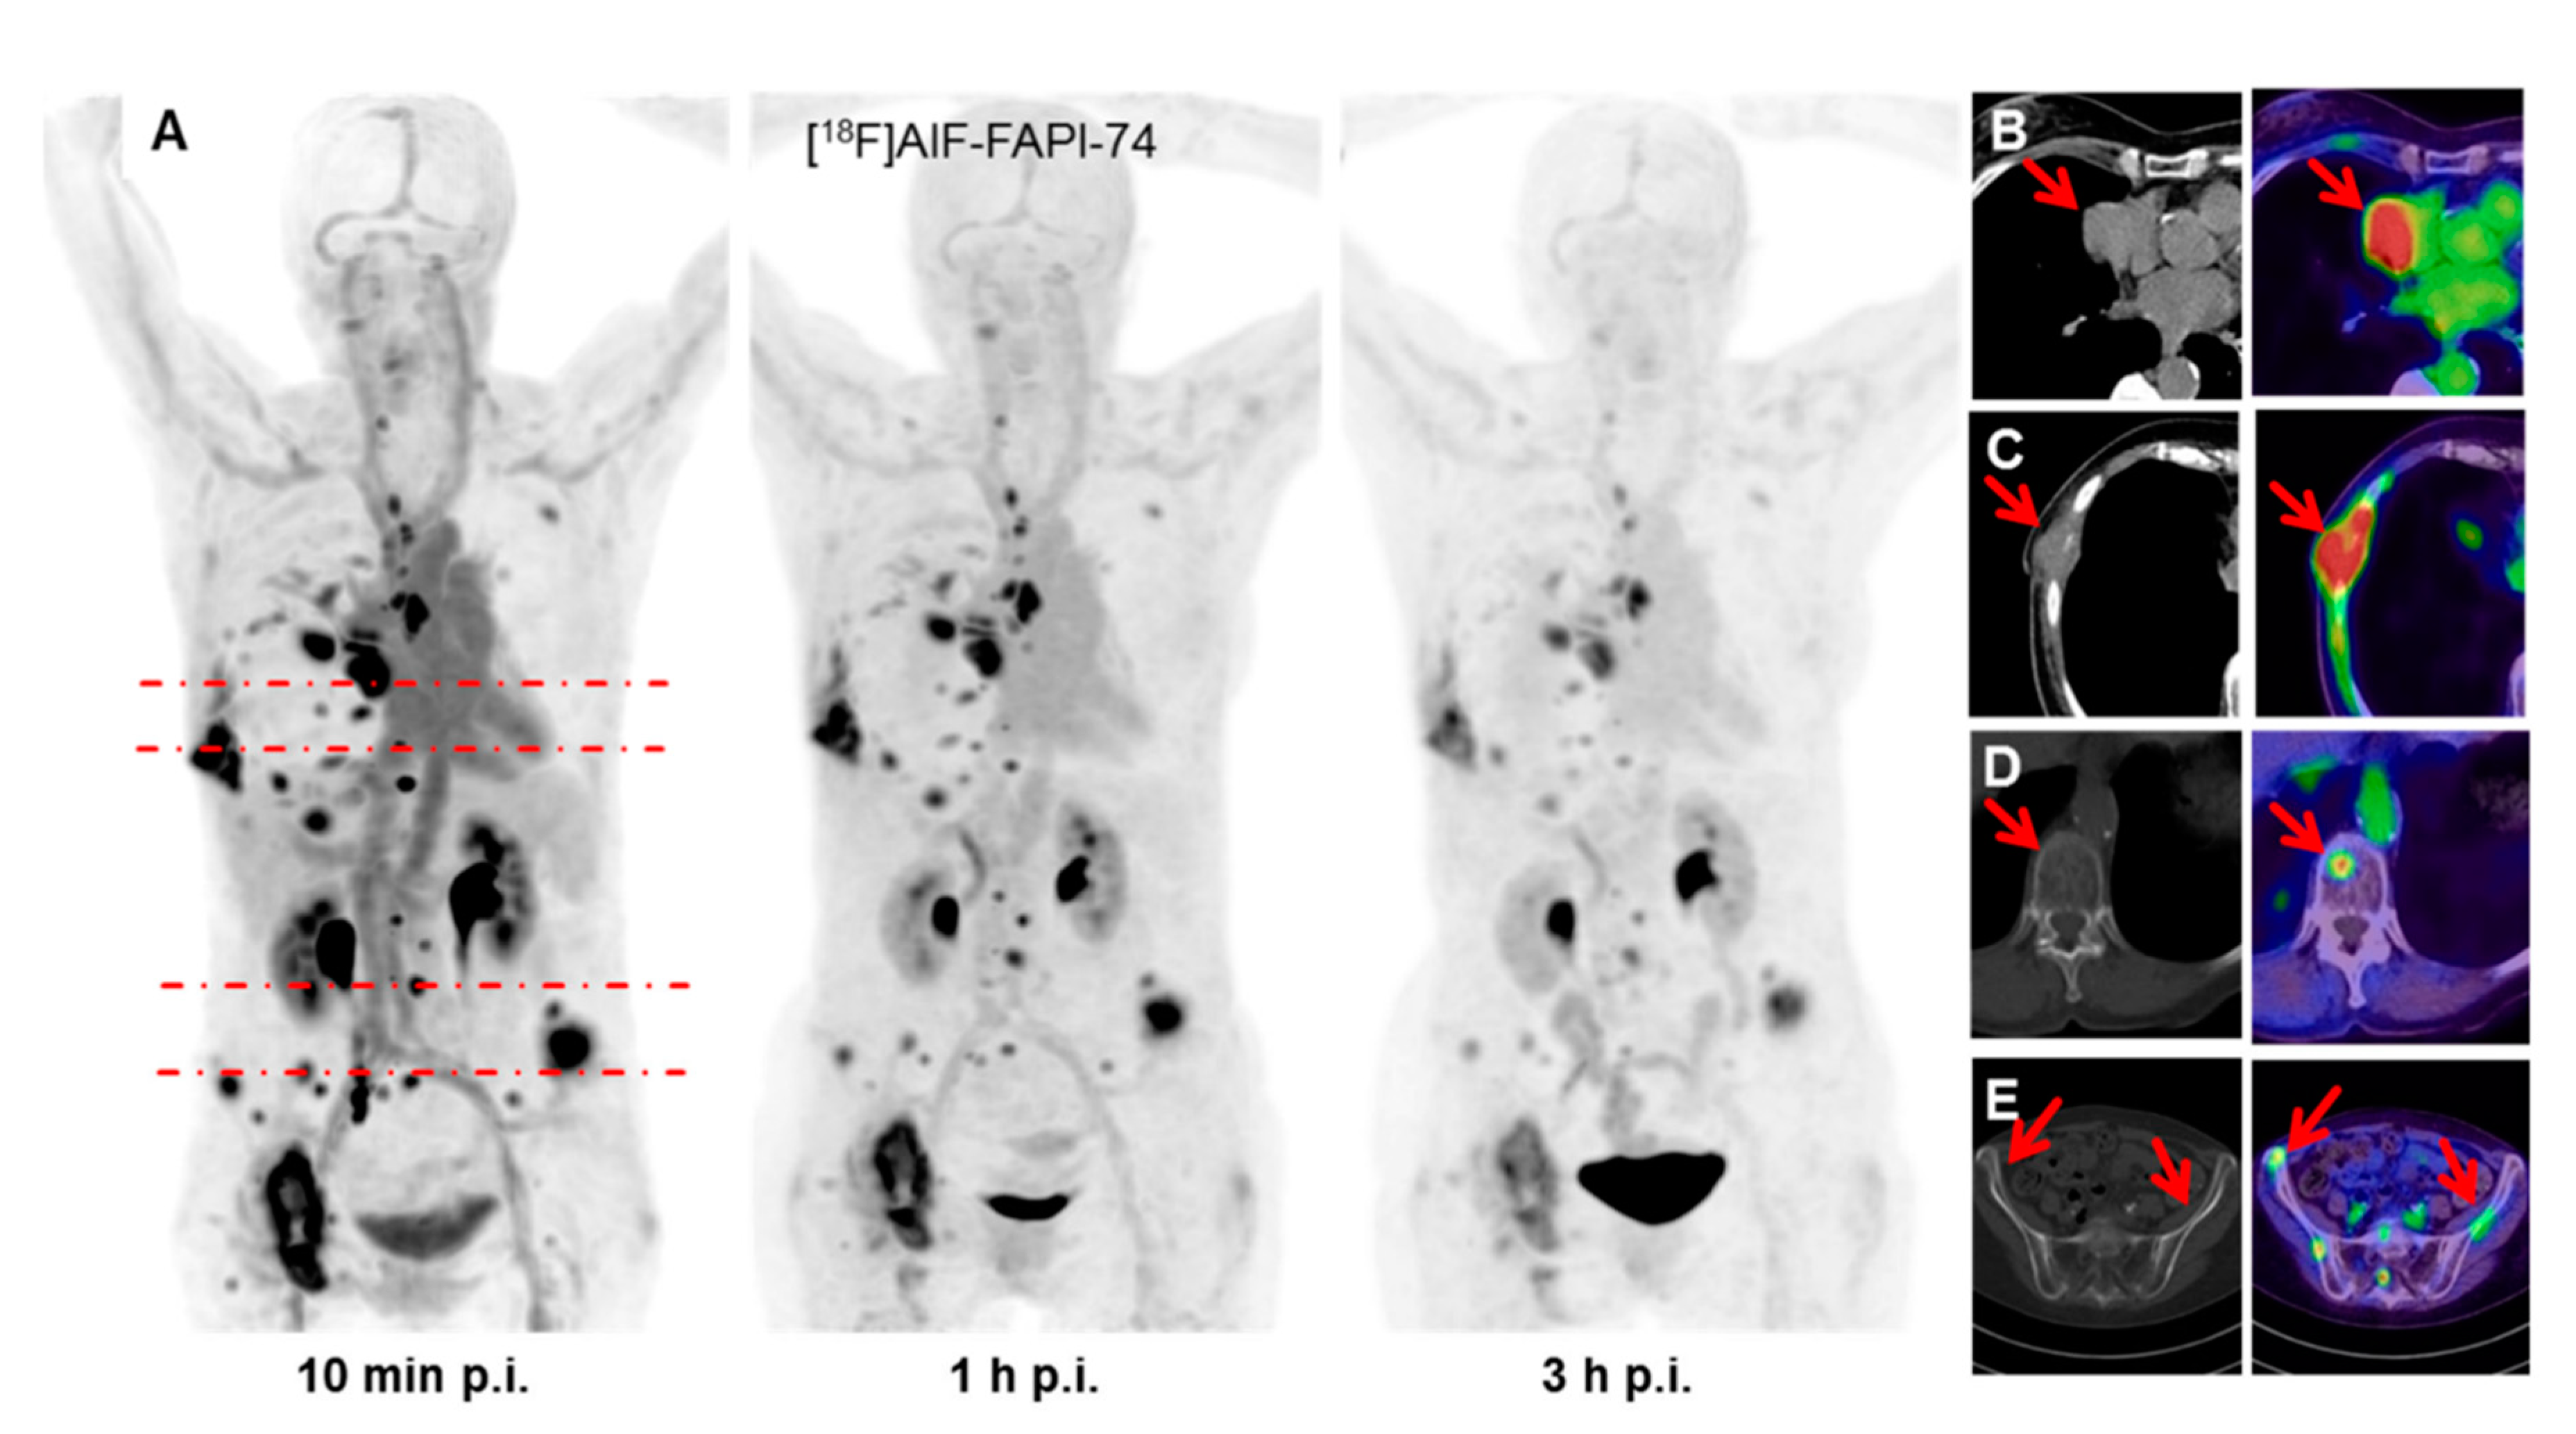

- Giesel, F.; Adeberg, S.; Syed, M.; Lindner, T.; Jimenez, L.D.; Mavriopoulou, E.; Staudinger, F.; Tonndorf-Martini, E.; Regnery, S.; Rieken, S.; et al. FAPI-74 PET/CT Using Either 18F-AlF or Cold-kit 68Ga-labeling: Biodistribution, Radiation Dosimetry and Tumor Delineation in Lung Cancer Patients. J. Nucl. Med. 2020. [Google Scholar] [CrossRef] [PubMed]

| FAPI-74 PET/CT Using Either 18F-AlF or Cold-kit 68Ga-labeling: Biodistribution, Radiation Dosimetry and Tumor Delineation in Lung Cancer Patients | Giesel, Adeberg et al. [24] | 2020 |

|

| Patent application, Shares in Consultancy group | none |